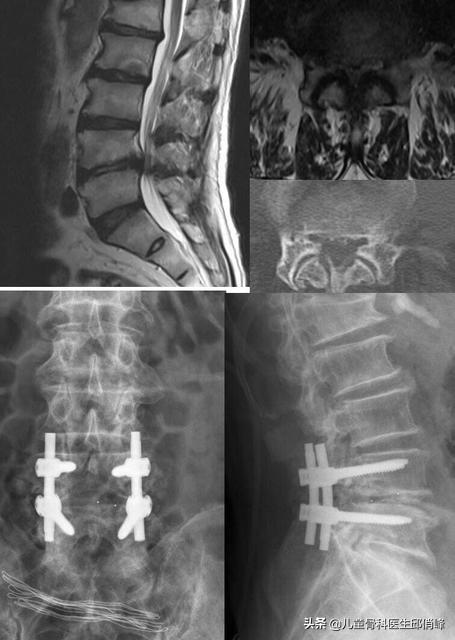

椎间盘膨出或者突出,都是需要持之以恒的,如果过于严重或者突出的椎间盘已经钙化,持续腰腿疼痛麻木,或者会阴部出现麻木等症状,或者保守治疗无效,严重影响了工作生活,也需要手术!